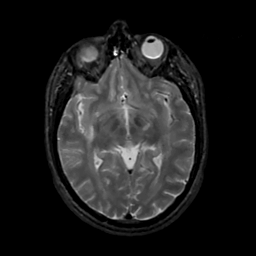

MR Study #10, April 28, 1991 -- Slice #23